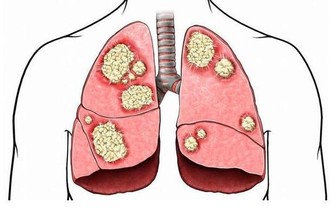

15.自感頭痛、腰痛、身痛,而又查不出器質性的病因。